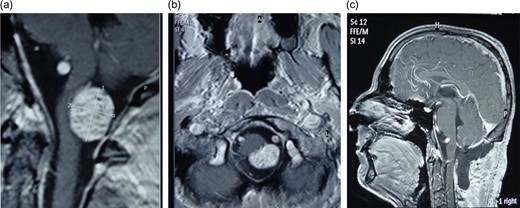

The first of our patients was a 43 years-old man who presented with a space-occupying lesion (SOL) in the cisterna magna adjacent to foramen magnum (FM). His main complaints were neck pain and headache accompanied by dizziness and tinnitus. His magnetic resonance imaging (MRI) revealed a well-circumscribed tumor abutting FM demonstrating high intensity on T1-post contrast sequences and measuring 1.6 × 2.1 cm (Fig. 1a and b). The patient underwent a midline suboccipital craniectomy and C1 laminectomy. Neurophysiologic monitoring was carried out but uneventful. A wound revision followed, due to postoperative complication by cerebrospinal fluid (CSF) leakage and meningitis, requiring prolonged hospitalization for antibiotics administration. Postoperative MRI revealed no tumor residuum (Fig. 1c). The patient was discharged relieved of pain and without new neurological deficit.

(a) MRI scan of first patient-Accesory nerve neurinoma sagittal plan (b) axial plane showing medulla attachment (c) postoperative MRI scan showing total tumor resection.